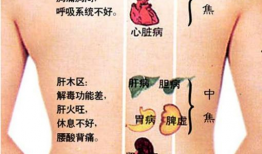

怎么刮痧背部视频教程,轻松掌握背部刮痧技巧

你有没有试过那种感觉,背上的肌肉像是被小怪兽抓挠,又酸又痛,让人坐立不安?别担心,今天我要给你带来一个超级实用的技能——刮痧!刮...